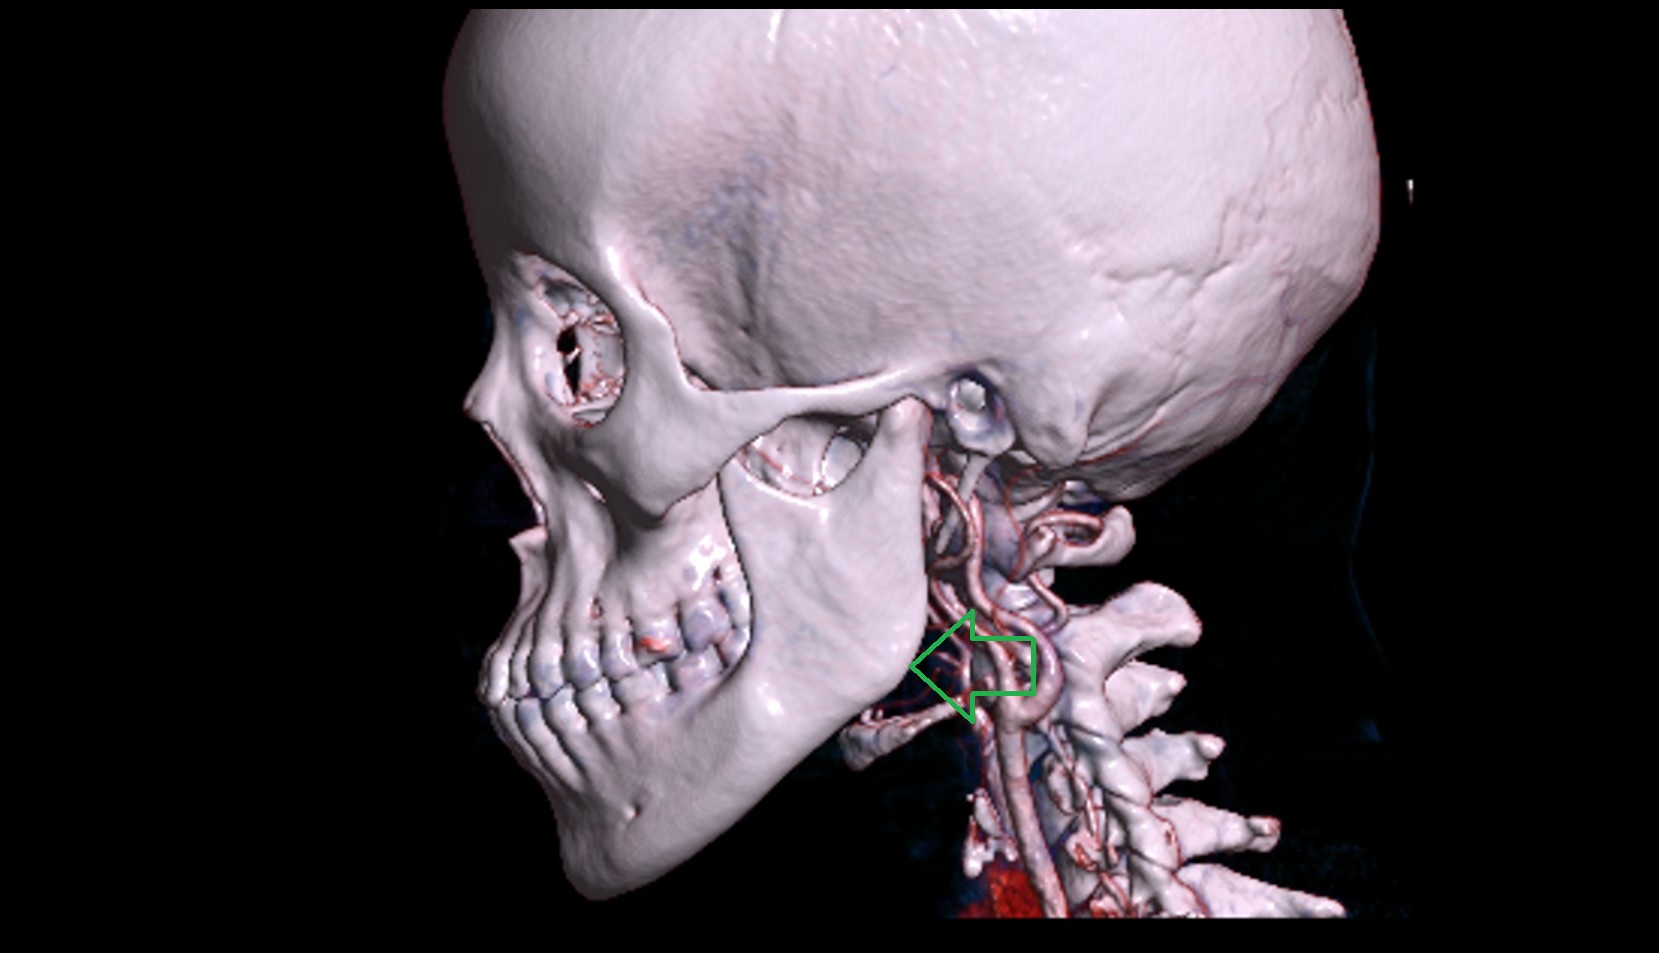

- Carotid bifurcation

- Internal carotid artery (cervical part)

- Right vertebral artery

- Left vertebral artery

- Right vertebral artery (cervical part)

- Right vertebral artery (atlantic part)

- Left vertebral artery (atlantic part)

- Left vertebral artery (cervical part)